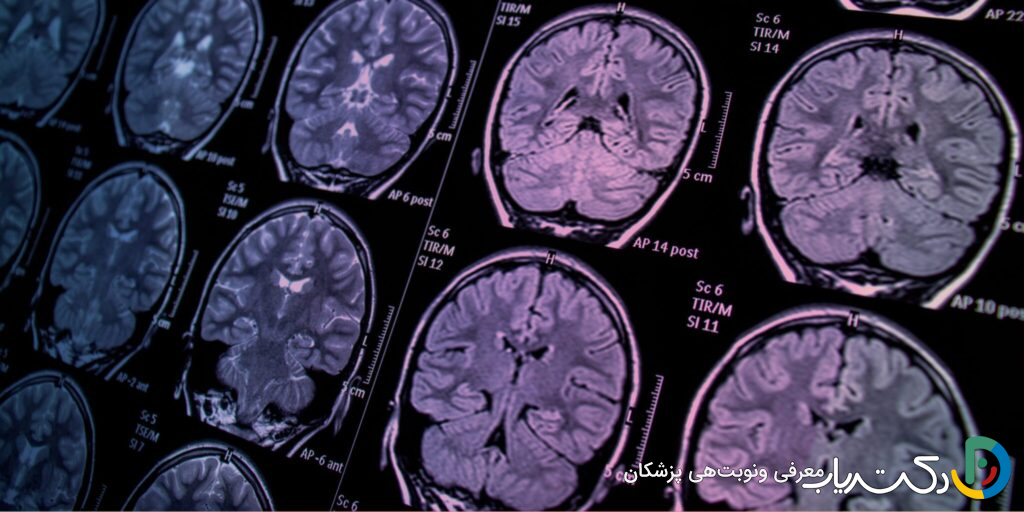

- تشخیص قطعی با تصویربرداری: تنها راه مطمئن برای تشخیص یا رد وجود تومور مغزی، استفاده از روشهای تصویربرداری پیشرفته مانند MRI است.

تصویربرداری مغز: استاندارد طلایی تشخیص

اگر نتایج تاریخچه پزشکی و معاینه عصبی مشکوک باشد، گام بعدی تصویربرداری از مغز است. این تنها راه برای تأیید یا رد قطعی وجود تومور و مشاهده مستقیم ساختار مغز است.

- MRI (تصویربرداری رزونانس مغناطیسی): این روش بهترین، دقیقترین و حساسترین ابزار برای مشاهده بافت نرم مغز و تشخیص تومورهاست. اغلب با تزریق یک ماده حاجب (کنتراست) انجام میشود. این ماده از طریق ورید تزریق شده و در نواحیای که سد خونی-مغزی (یک سد محافظ طبیعی) آسیب دیده است، مانند اطراف تومورها، تجمع مییابد و باعث میشود تومور در تصاویر MRI به صورت یک ناحیه درخشان و بسیار واضح دیده شود.

- CT Scan (توموگرافی کامپیوتری): این روش سریعتر از MRI است و در شرایط اورژانسی یا در بیمارستانهایی که MRI در دسترس نیست، بیشتر استفاده میشود. اگرچه به اندازه MRI برای بافت نرم دقیق نیست، اما میتواند وجود تودههای بزرگ، خونریزی، تورم شدید یا هیدروسفالی را بهخوبی نشان دهد.